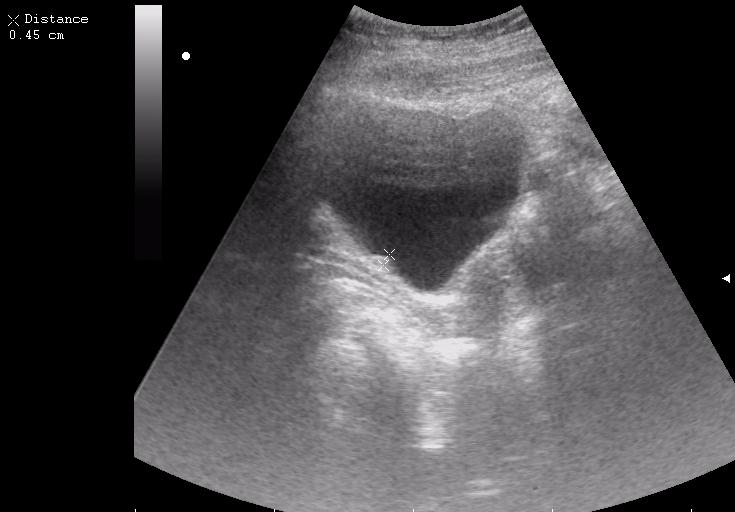

Сравните

Продольное сканирование мочевого пузыря После легкой перкуссии мочевого пузыря

ну... и сравнивать нечего, обычно так выглядят болота в Белоруссии, или первые 2 дня о.цистита